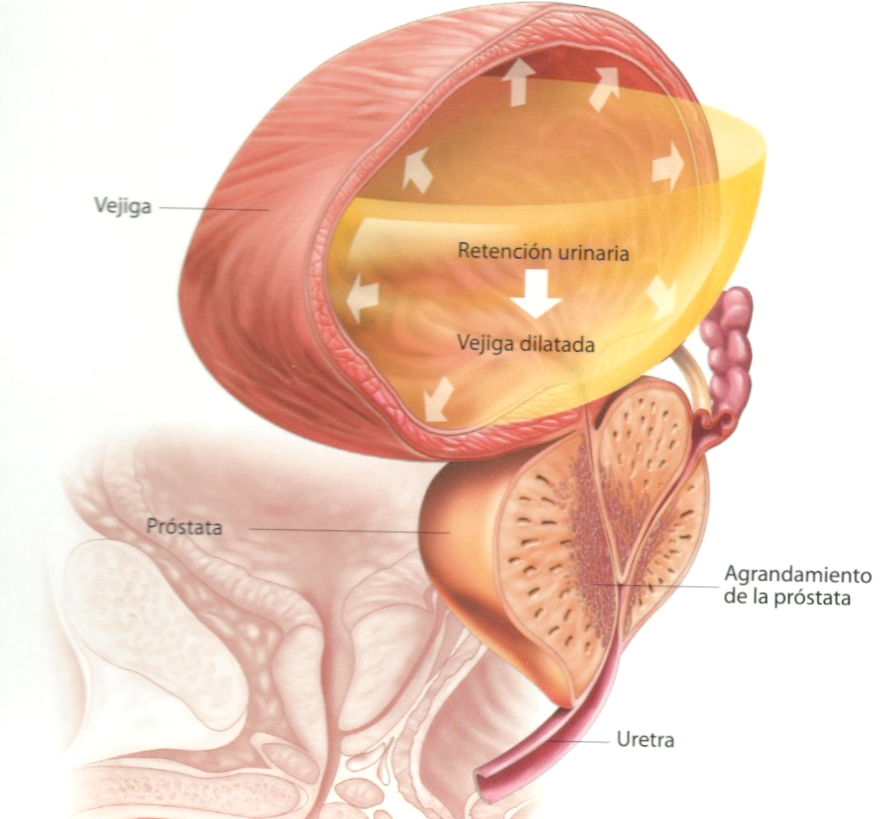

La próstata es un órgano del sistema reproductor del varón. Es una glándula, con forma de castaña, colocada debajo de la vejiga y por delante del recto. La uretra (conducto por donde sale la orina) atraviesa la próstata por el centro, de manera que la orina sale de la vejiga atravesando la próstata. Las posibles enfermedades de la próstata comprimen la uretra y producen molestias al orinar.